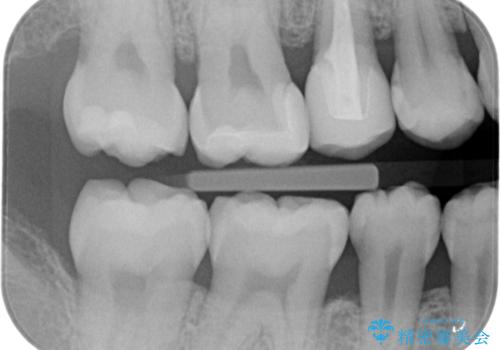

歯と歯の間の虫歯 セラミックインレーでの修復処置

- 検査の結果、歯と歯の間に虫歯が確認された患者様です。

虫歯を除去した後、セラミックインレーで修復処置を行います。

レントゲン画像では写りにくい小さな虫歯も発見したため、そこも含めた形での修復処置を行いました。